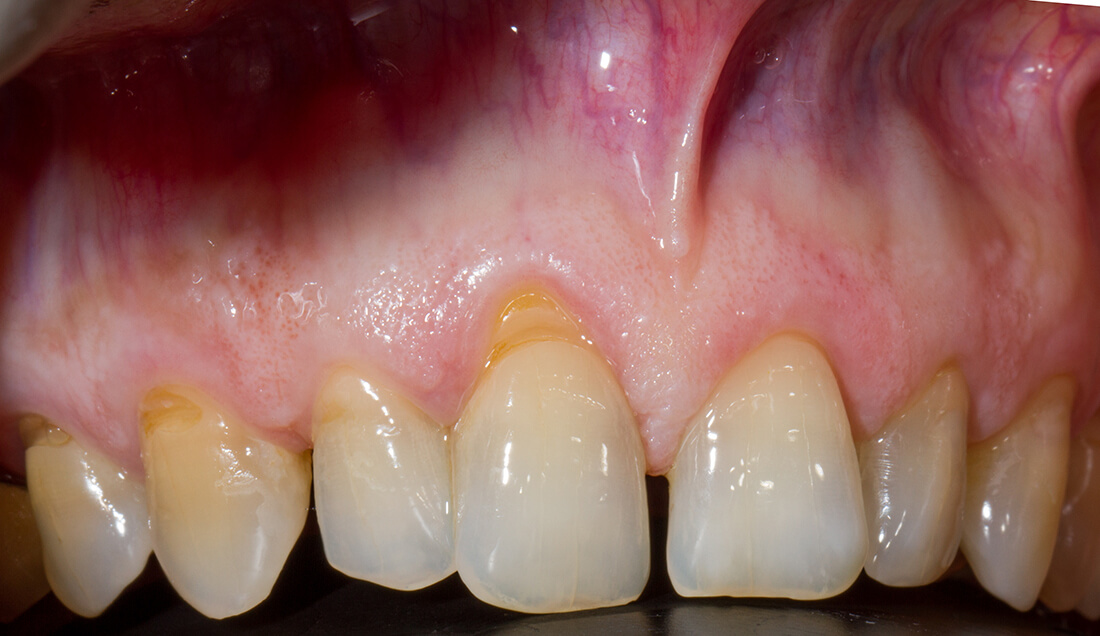

Esempio di recessione gengivale

Recessione Gengivale

La recessione gengivale è una patologia dentale che riguarda il ritiro della gengiva verso il margine apicale del dente, la zona che corrisponde alla radice del dente.

Questa situazione, oltre ad essere esteticamente disturbante, può portare ad avere ulteriori disagi, come ipersensibilità dentale, infiammazione e formazione di carie sulla radice che si scopre. Visivamente la recessione gengivale si presenta con la forma più allungata dei denti, proprio a causa del ritiro della gengiva che scopre parte della radice.